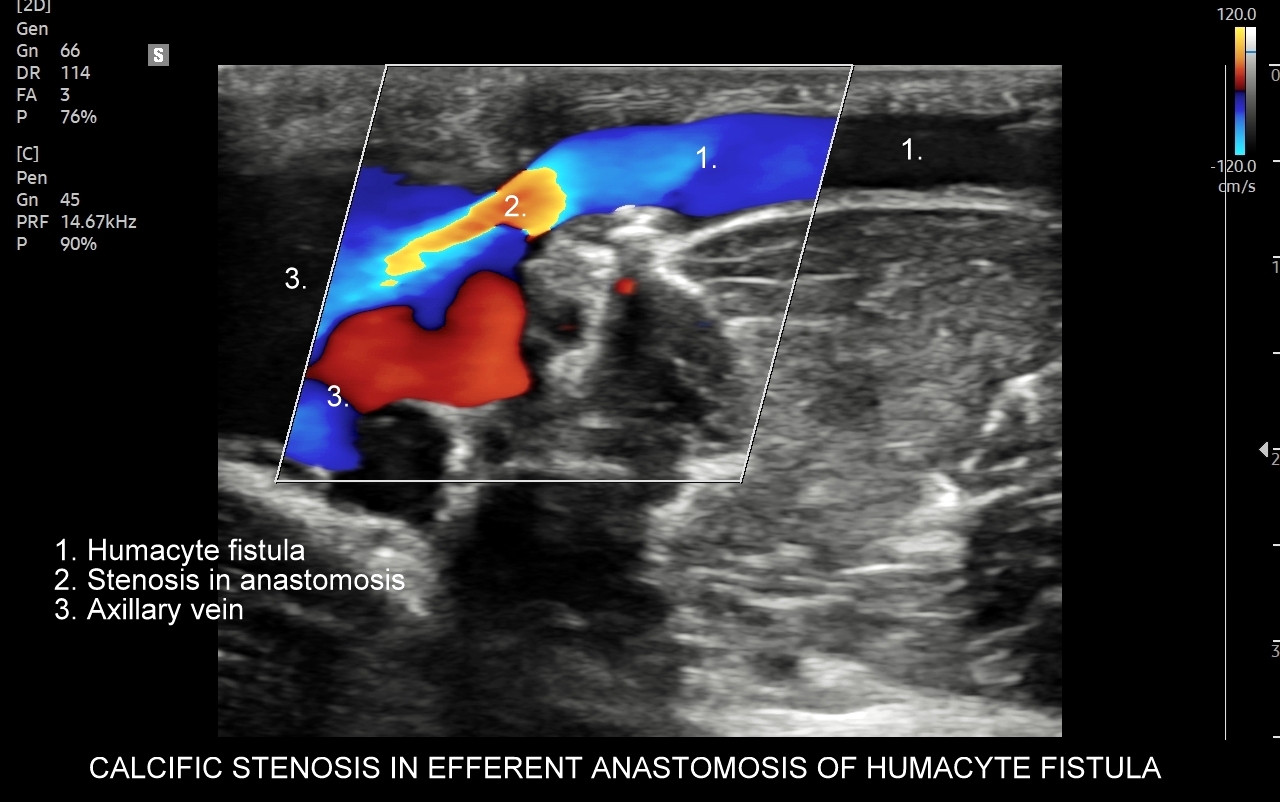

Przetoka dializacyjna to chirurgicznie wytworzone połączenie tętniczo-żylne, które wykorzystywane jest do przewlekłego leczenia nerkozastępczego w formie hemodializy u pacjentów z niewydolnością nerek. Badanie USG Doppler jest podstawową metodą diagnostyczną oceniającą dojrzałość przetoki i jej gotowość do dializy, prawidłowość zespoleń naczyniowych, drożność przetoki oraz objętość przepływu minutowego. W Pracowni dr Tomasza Szczepańskiego zbadać można klasyczne przetoki tętniczo-żylne, jak również zaawansowane przetoki Humacyte ®.